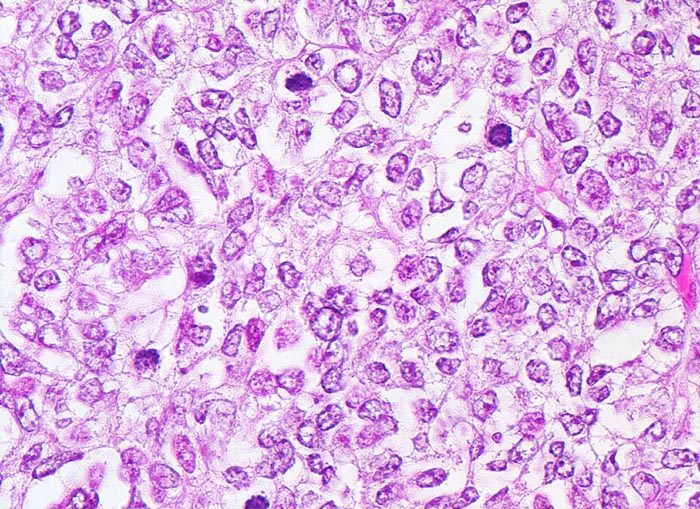

Neben dem endometrioiden Adenokarzinom gibt es noch weitere, hormon-unabhängige und klinisch aggressive Formen, wie beispielsweise das seröse Adenokarzinom und das klarzellige Karzinom. Als Vorstufe der serösen Adenokarzinome gilt das seröse intraepitheliale Karzinom (=SEIC) Letzteres kann trotz fehlender Invasion ausgedehnt metastasieren.

• Anstelle des Endometriums findet sich in der linken Hälfte des Uteruskavums ein Adenokarzinom bestehend aus architektonisch komplexen Drüsen. Die Drüsen liegen teils dos à dos ohne erkennbares Stroma zwischen zwei Drüsenschläuchen.

• Tumorzellverbände infiltrieren die glatte Muskulatur des Myometriums.

• Tumordrüsen ausgekleidet von mehrreihig angeordneten Tumorzellen mit hyperchromatischen polymorphen längsovalen Tumorzellkernen mit zahlreichen Mitosen. Die Morphologie der Tumordrüsen erinnert an proliferatives Endometrium.